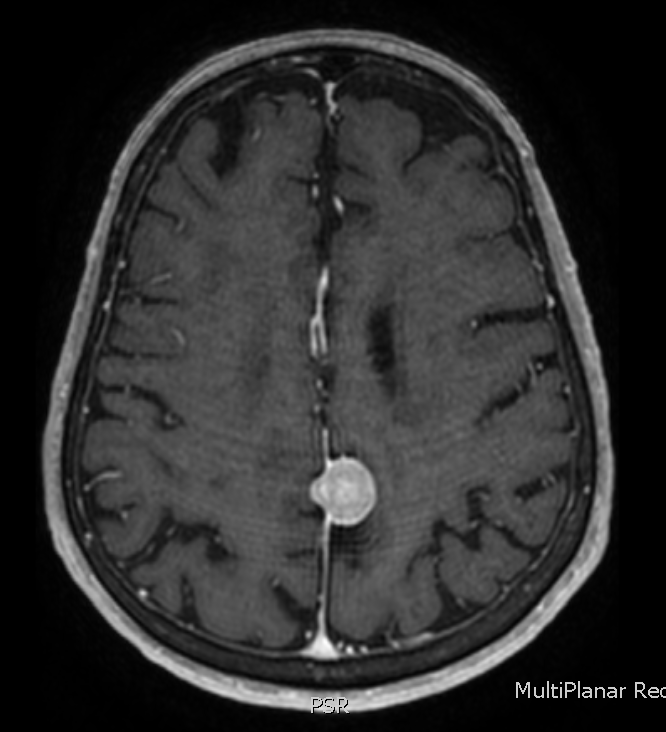

The answer is 2) the lesion is extra-axial. Take a look at the brain MRI’s below to prove it to yourself.

Now, which of the following is true? (scroll down for the answer)

The answer is 1) these lesions often contain small bits of calcium, called psammoma bodies. You have probably guessed by now that General Wood had a meningioma – a brain tumor that is usually benign, although they can cause significant symptoms depending on their location and degree of mass effect. Meningioma’s rarely recur after surgical resection, although unfortunately for General Wood, his did.

Meningiomas should be broad based to the dura, as is the example shown here, which grows out of the falx cerebri. Most are sporadic, but exposure to ionizing radiation is a risk factor for late life meningiomas.